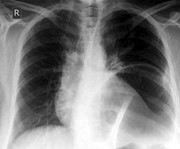

Fatal broncho-pulmonary artery fistula after lobectomy for lung cancer

Jiro Abe and others

Journal of Surgical Case Reports, Volume 2015, Issue 9, September 2015, rjv110, https://doi.org/10.1093/jscr/rjv110